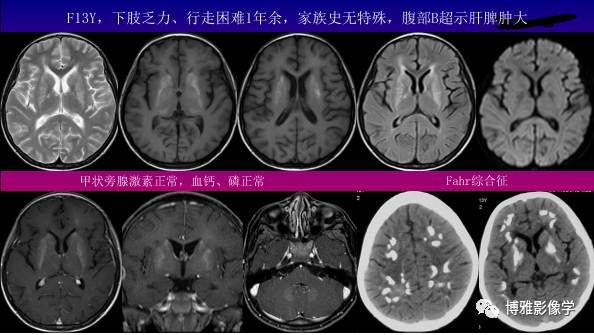

中枢神经系统病变基本成分信号特点